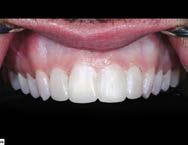

Estudio de caso

El paciente se presentó después de varios años de sufrir una herida traumática en sus dientes anterio res superiores. Las piezas 11 y 21 tenían varias fracturas, así como el borde incisal de la pieza 12. Por lo que él deseaba mejorar su estética bucal, y yo quería asegurarme de restaurar la funcionalidad y resisten cia también. El paciente necesitaba completar su tratamiento en un cor to periodo de tiempo, por ello debí realizar ajustes en mi flujo de traba jo. (Figura 1).

Las carillas BruxZir Esthetic fueron justo lo que el paciente esperaba y la emoción por su nueva sonrisa era evi dente (Figura 15).